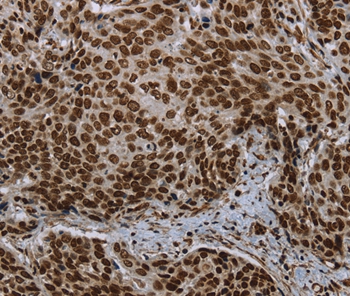

Immunohistochemical analysis of paraffin-embedded Human cervical cancer tissue using #37702 at dilution 1/20.

Immunohistochemical analysis of paraffin-embedded Human thyroid cancer tissue using #37702 at dilution 1/20.